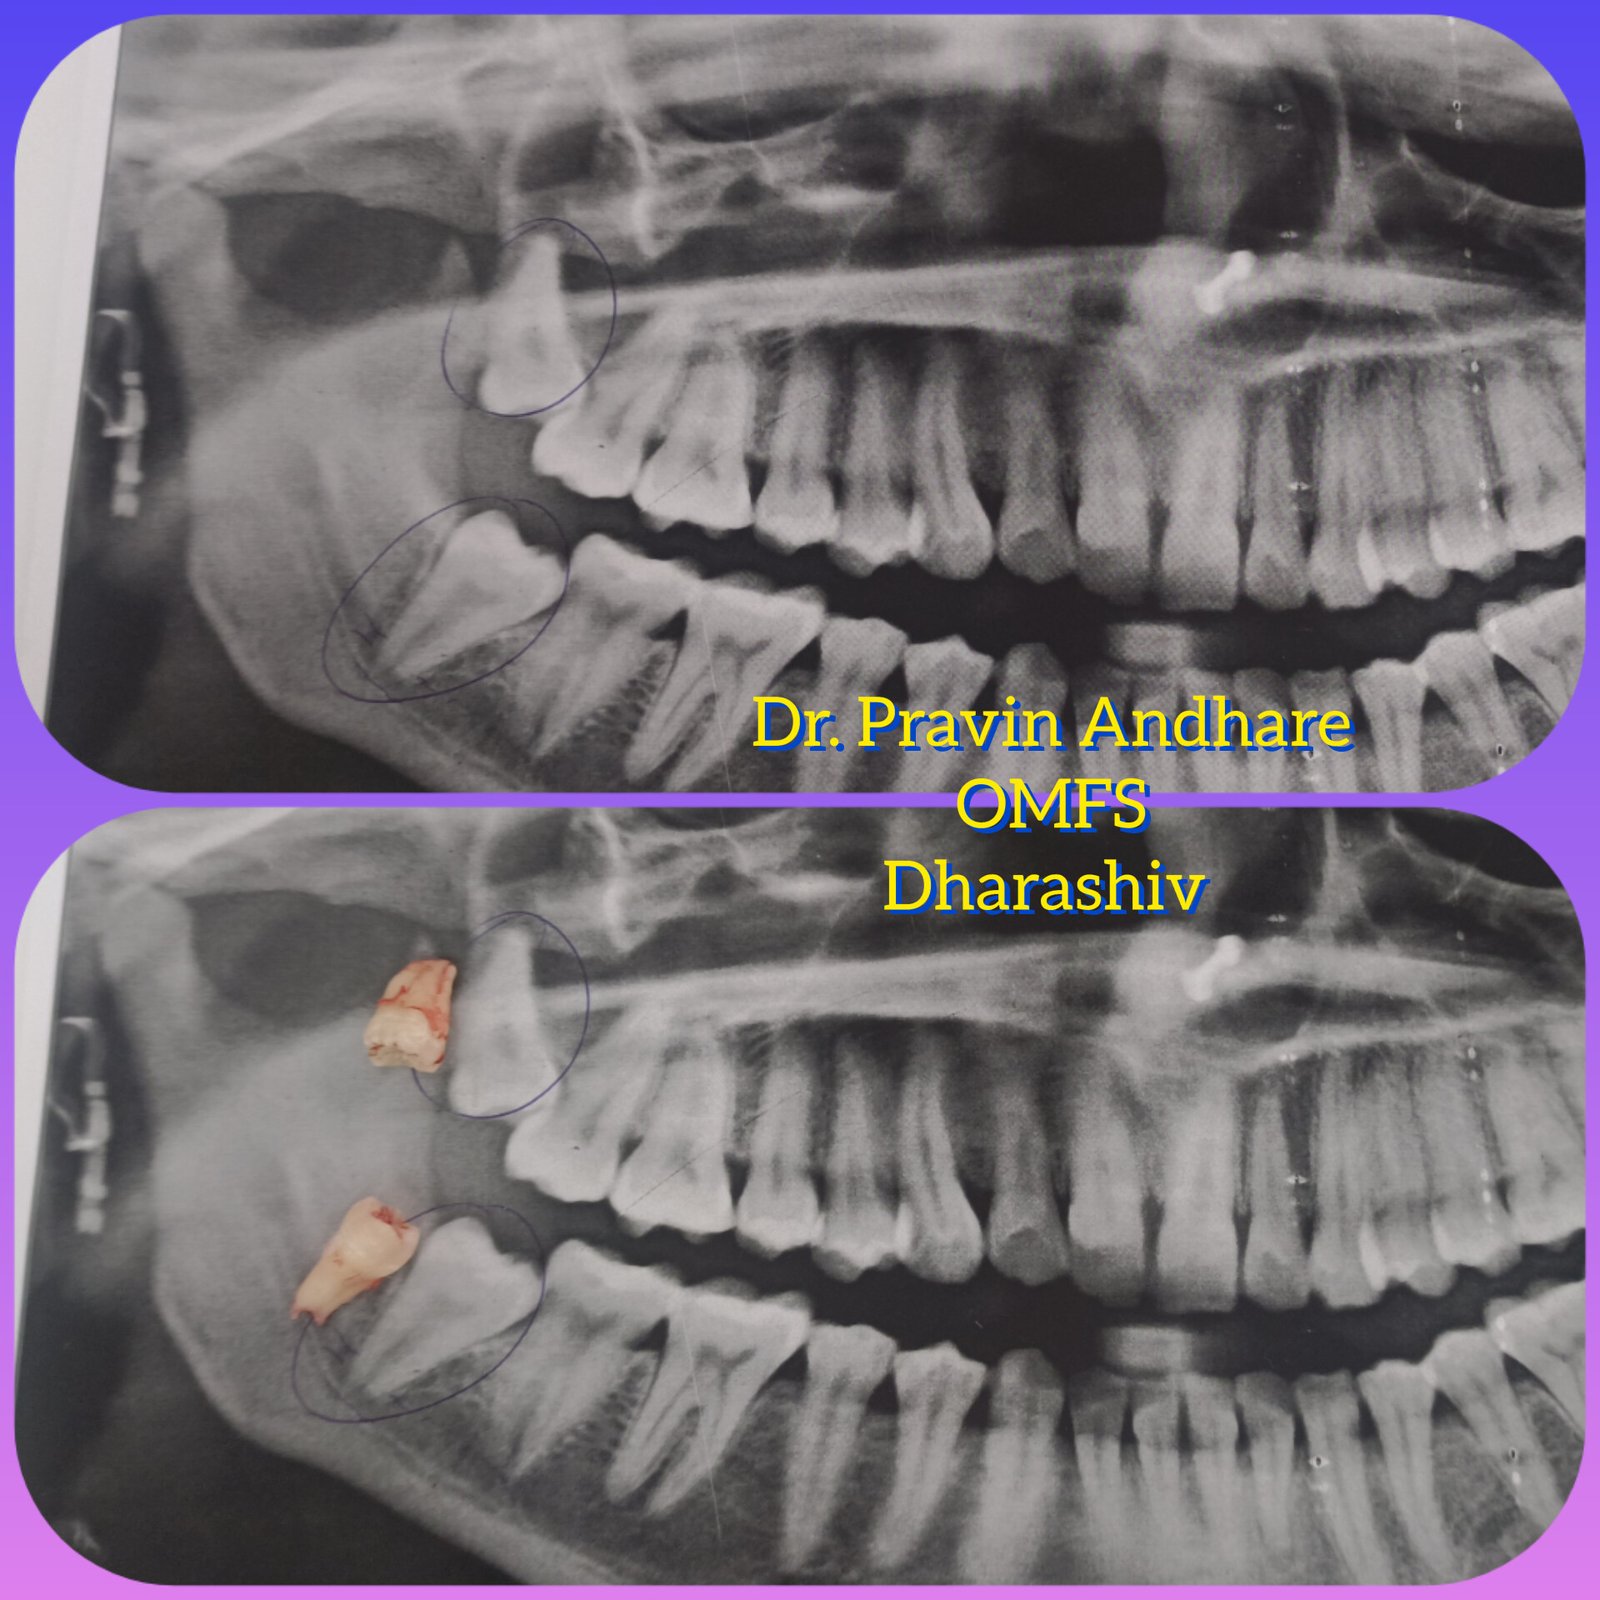

ЁЯПе рдзрд╛рд░рд╛рд╢рд┐рд╡ рдЬрд┐рд▓реНрд╣реНрдпрд╛рддреАрд▓ рдкреНрд░рд╕рд┐рджреНрдз рдбреЗрдВрдЯрд▓ рд╣реЙрд╕реНрдкрд┐рдЯрд▓ & рдлреЗрд╢рд┐рдпрд▓ рдЯреНрд░реЙрдорд╛ рдХреЗрдЕрд░ рд╡ рдЗрдореНрдкреНрд▓рд╛рдВрдЯ рд╕реЗрдВрдЯрд░ ЁЯПе ЁЯПердЕрддреНрдпрд╛рдзреБрдирд┐рдХ рдбрд┐рдЬрд┐рдЯрд▓ рдПрдХреНрд╕-рд░реЗ ЁЯПердЗрдВрдЯреНрд░рд╛ рдУрд░рд▓ рдХреЕрдореЗрд░рд╛ рджреНрд╡рд╛рд░реЗ рддрдкрд╛рд╕рдгреА ЁЯж╖рдЕрд▓реНрдЯреНрд░рд╛рд╕реЛрдирд┐рдХ рдорд╢реАрдирджреНрд╡рд╛рд░реЗ рджрд╛рдд рд╕рд╛рдл рдХрд░рдгреЗ ЁЯж╖рдХреГрддреНрд░рд┐рдо рджрдВрддрд░реЛрдкрдг ЁЯж╖рдЕрдХреНрдХрд▓рджрд╛рдбреЗ рд╡рд░реАрд▓ рд╢рд╕реНрддреНрд░рдХреНрд░рд┐рдпрд╛ ЁЯж╖рдЬрдмрдбреНрдпрд╛рдВрдЪреЗ рдлреНрд░реЕрдХреНрдЪрд░ рд╡рд░реАрд▓ рд╢рд╕реНрддреНрд░рдХреНрд░рд┐рдпрд╛ ЁЯзмрдЕрддреНрдпрд╛рдзреБрдирд┐рдХ рдкрджреНрдзрддреАрдиреЗ рджрд╛рддрд╛рдВрдЪреНрдпрд╛ рдирд╕рд╛ рд╡рд░реАрд▓ рдЙрдкрдЪрд╛рд░ ЁЯзмрддреЛрдВрдбрд╛рддреАрд▓ рдореМрдЦрд┐рдХ рд╢рд╕реНрддреНрд░рдХреНрд░рд┐рдпрд╛ ЁЯзмрд╕рдВрдкреВрд░реНрдг рдХрд┐рдВрд╡рд╛ рдЕрдВрд╢рддрдГ рдХрд╡рд│реА рдмрд╕рд╡рдгреЗ ЁЯзмрд╡реЗрдбреЗрд╡рд╛рдХрдбреЗ рджрд╛рдд рд╕рд░рд│ рдХрд░рдгреЗ

ЁЯПе рдлреЗрд╢рд┐рдпрд▓ рдЯреНрд░реЙрдорд╛ рдХреЗрдЕрд░ рд╡ рдЗрдореНрдкреНрд▓реЗрдВрдЯ рд╕реЗрдВрдЯрд░

ЁЯПе рддреЛрдВрдбрд╛рддреАрд▓ рдореМрдЦрд┐рдХ рд╢рд╕реНрддреНрд░рдХреНрд░рд┐рдпрд╛ рд╕реНрдкреЗрд╢рд╛рд▓рд┐рд╕реНрдЯ